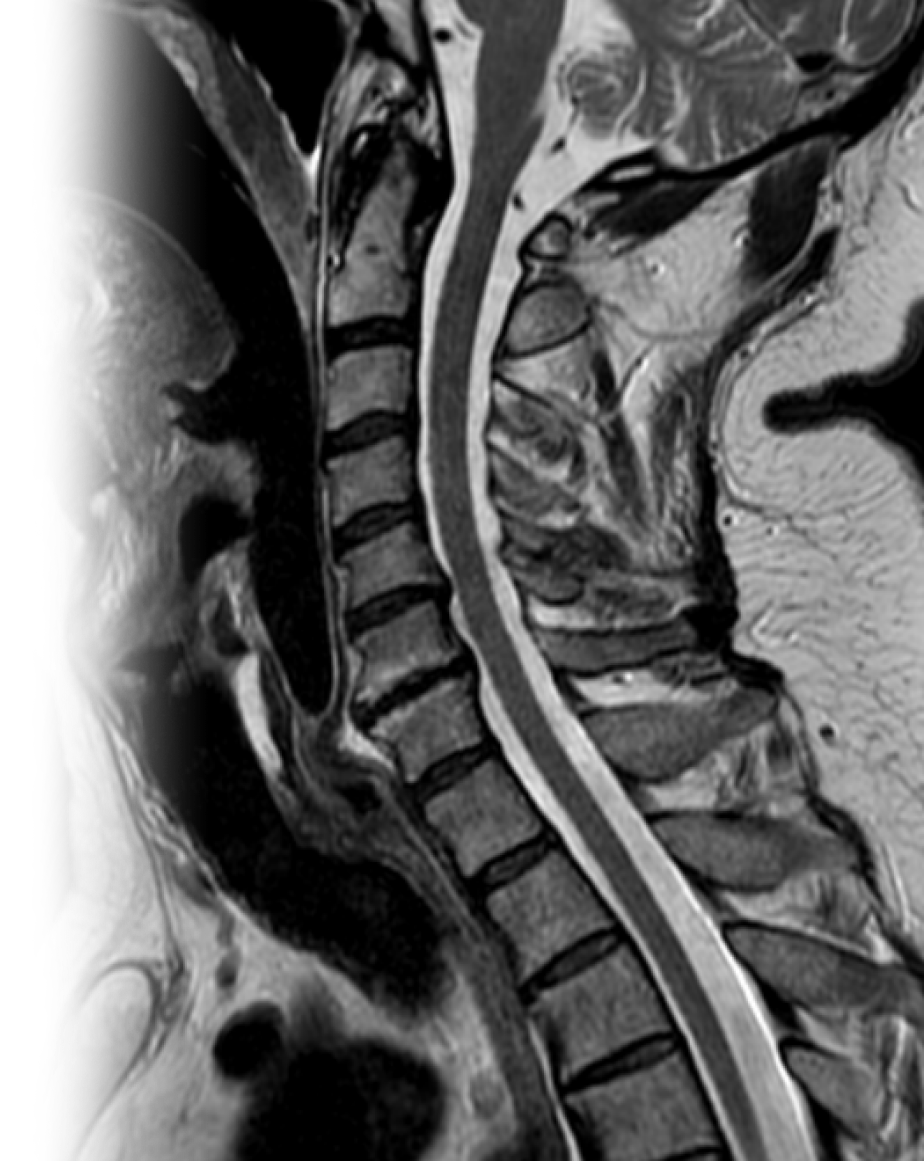

МРТ шейного отдела позвоночника МРТ шейного отдела позвоночника

МРТ шейного отдела позвоночника

Магнитно-резонансная томография шейного отдела позвоночника – важный метод исследования, который позволяет оценить состояние шейного отдела позвоночника.

Также МРТ шейного отдела позвоночника может быть проведена с бесконтрастной ангиографией артерий шеи.